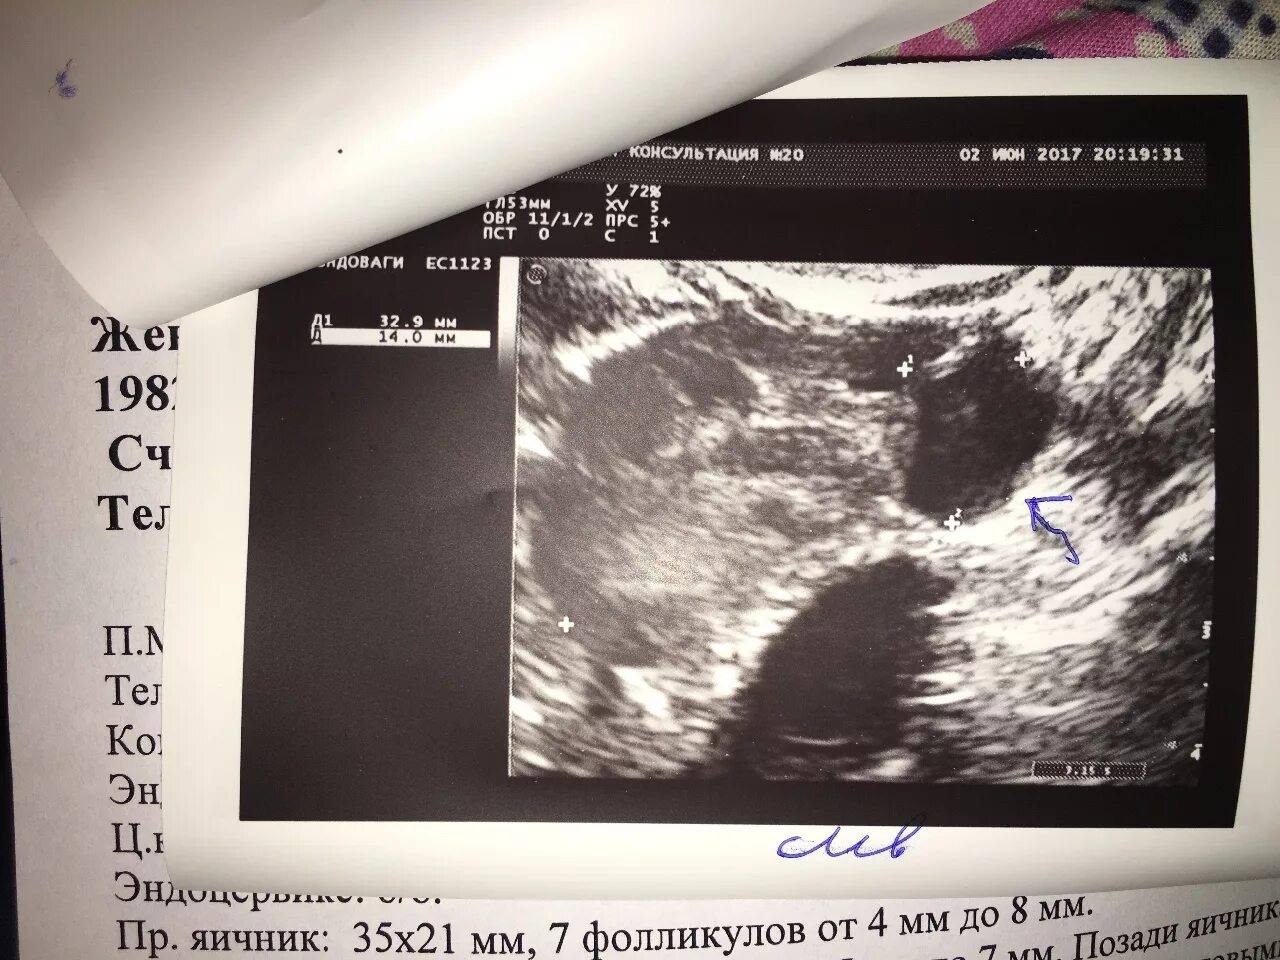

Что значит яичник не визуализируется на узи